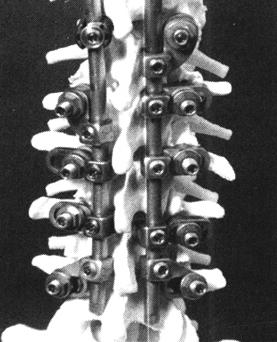

图13-55 22岁男性,L1爆裂骨折,后路CD固定,固定伤柱上二节和下一节